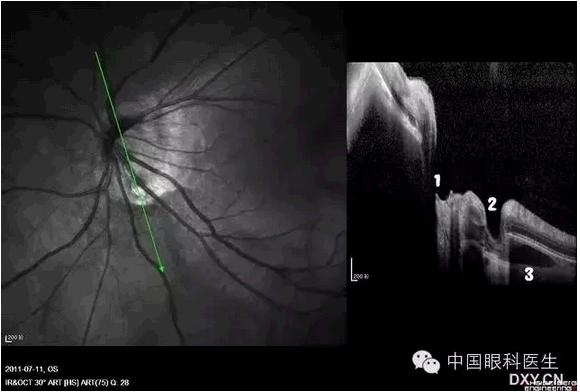

1、正常视盘凹陷位置

2、视盘小凹

3、脉络膜囊样暗区